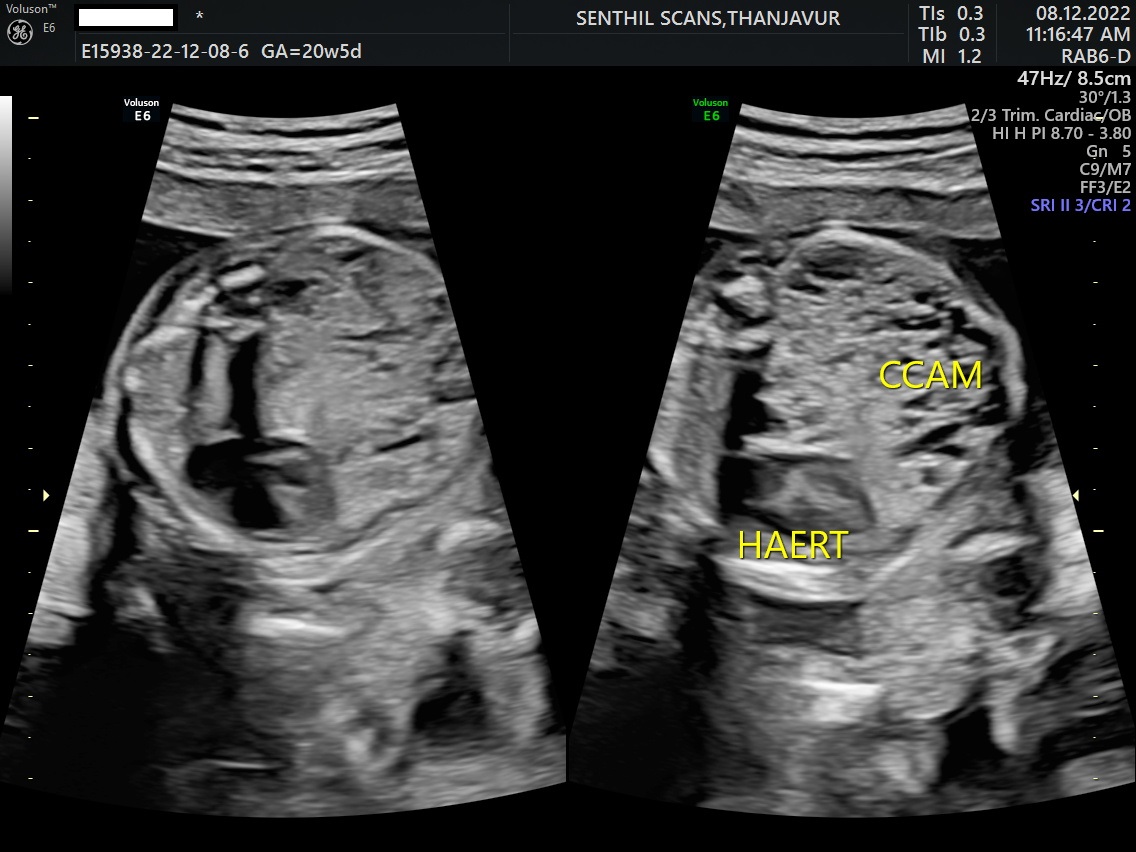

CCAM - Congenital Cystic Adenomatoid Malformation